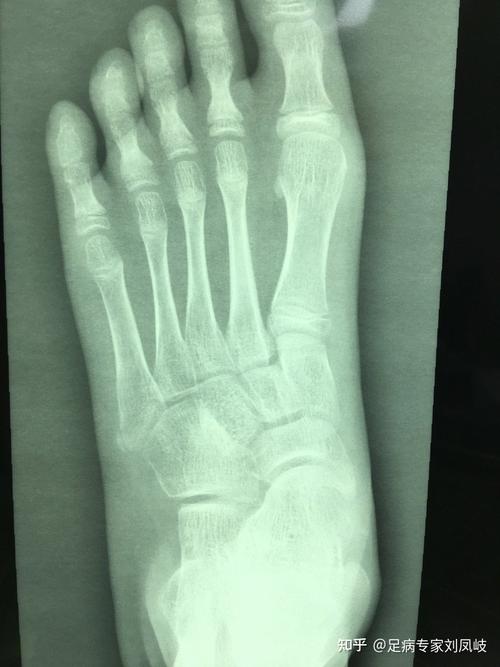

踝,x光片,跖骨,跟骨,手舟骨

10岁小孩跟骨x光片

小孩跟骨正常x光片

儿童跟骨x线图片

儿童踝关节正常x片